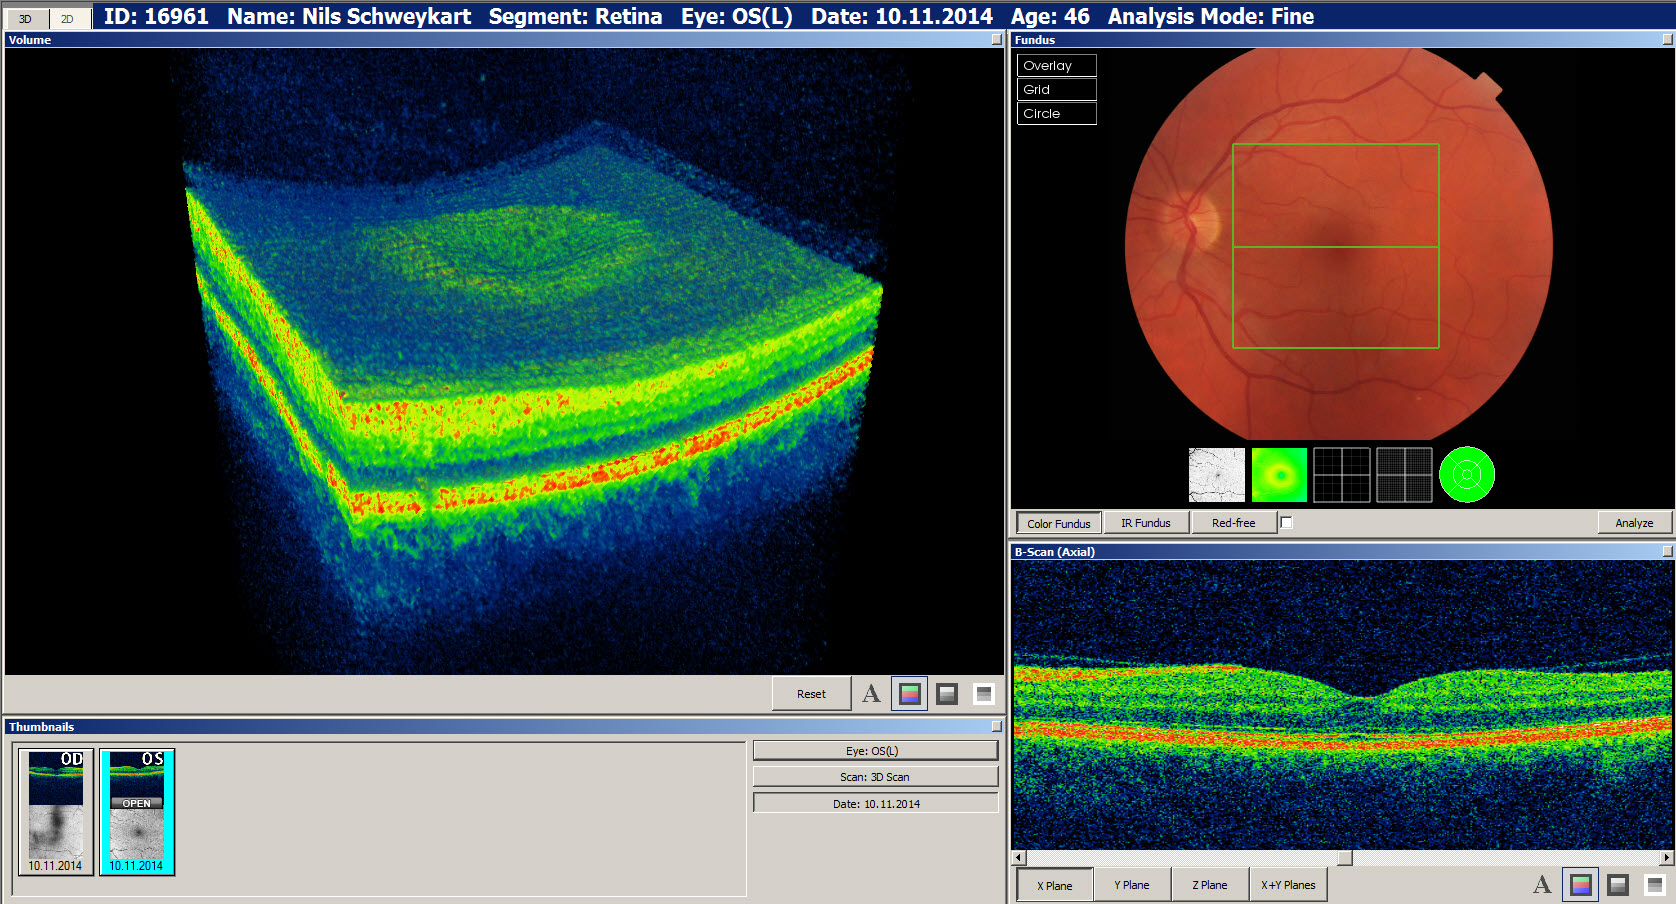

Ablauf der optischen Kohärenztomographie